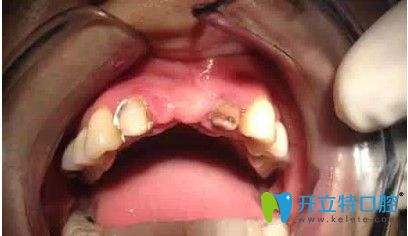

劉女士,33歲,據(jù)她描述,自己多年前在國(guó)內(nèi)一家口腔醫(yī)院做了烤瓷冠,但由于時(shí)間長(zhǎng)變的松動(dòng),考慮到自己還年輕,為了一步到位,她來(lái)韓國(guó)安特麗做了多顆牙種植。

在拆除烤瓷橋后,發(fā)現(xiàn)她的口內(nèi)埋伏牙,把埋伏牙拔除后,很順利的植入了種植體,完成了種植牙。